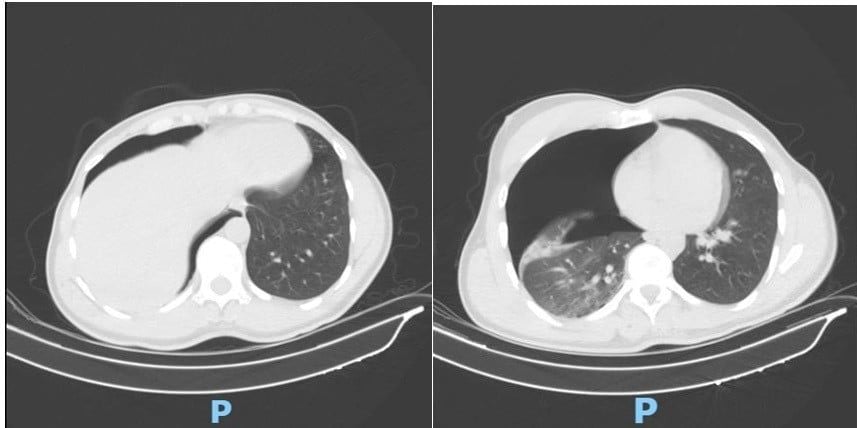

Phim CT scan lồng ngực sáng ngày nhập viện ghi nhận tràn khí màng phổi phải lượng nhiều

Ngay khi tiếp nhận, các bác sĩ đã khẩn trương thực hiện CT scan lồng ngực, mạch máu khẩn cấp. Kết quả cho thấy người bệnh bị tràn khí màng phổi phải lượng nhiều gây chèn ép phổi, gãy cung bên xương sườn 2, 3, 4 phải và gãy phức tạp 1/3 giữa xương đòn phải, di lệch nhiều kèm mảnh rời.

Trước nguy cơ suy hô hấp nặng, ê-kíp Khoa Phẫu thuật Tim – Lồng ngực – Mạch máu đã tiến hành đặt dẫn lưu màng phổi phải cấp cứu. Ca thủ thuật do TS-BS Đồng Đức Hưng trực tiếp thực hiện. Nhờ xử trí nhanh chóng, chính xác, phổi phải nở lại tốt, tình trạng hô hấp của người bệnh cải thiện rõ rệt chỉ sau vài giờ.

Sau hai ngày điều trị hậu phẫu, chức năng hô hấp đã ổn định và ống dẫn lưu được rút, người bệnh được chuyển sang Khoa Điều trị theo yêu cầu – Y học thể thao để tiếp tục xử trí chấn thương xương đòn.